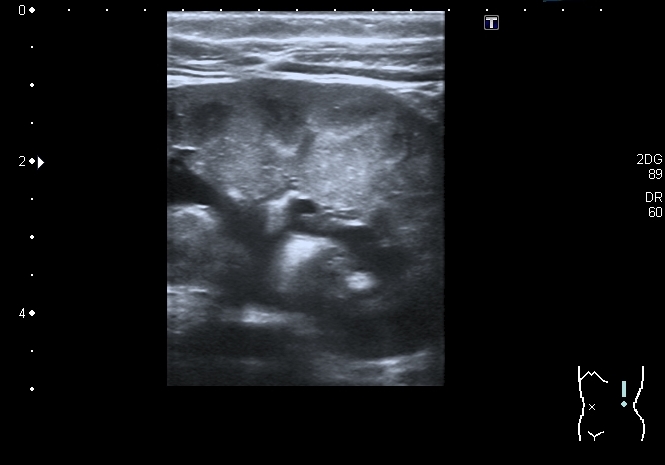

При УЗИ: правая почка - не изменена, в левой - незначительное расширение ЧЛС

В мочевом пузыре определяется достаточно большое уретероцеле слева, периодически увеличивающееся и пульсационное уретероцеле справа. Левый мочеточник в нижней трети резко расширен.